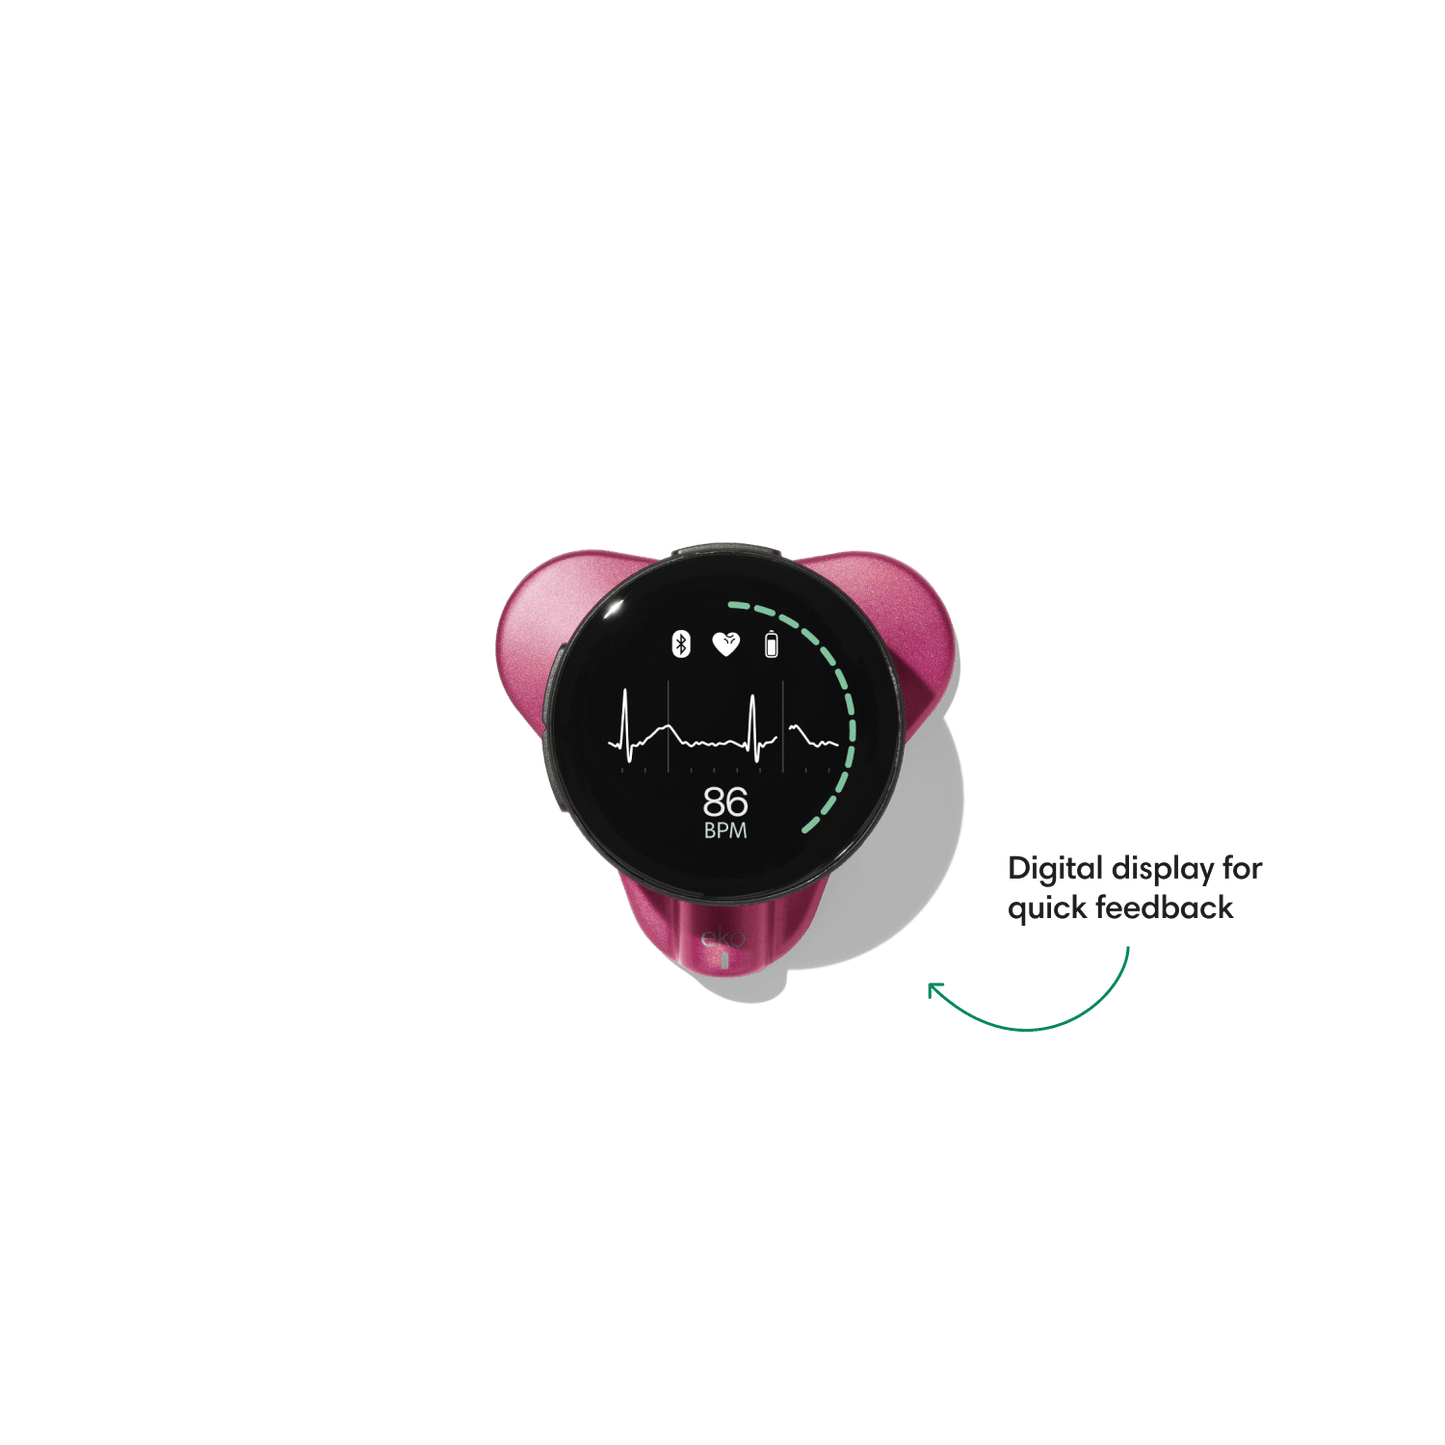

Go beyond sound alone.

For the first time ever, measure heart rate, visualize 3-lead ECG, and see detection results — right on a built-in, full-color display.